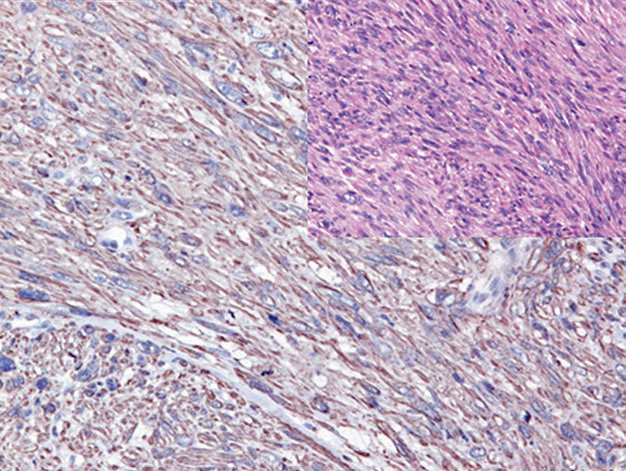

图2. 横纹肌肉瘤中,Myogenin(左)和MyoD1(右)在细胞核强阳性表达。

需要注意的是,这两种肌源性标记在非肿瘤性肌母细胞中均可为阳性,而这类细胞可见于修复性及萎缩性肌肉病变中。Myogenin和MyoD1的表达也曾报道于某些其他肿瘤,如韧带样瘤、婴儿型纤维肉瘤、Wilms瘤。Myogenin和MyoD1染色的解读中,仅有细胞核着色才能被视为阳性,其他着色方式(如胞质着色、细胞膜着色)都是无诊断意义的假象。